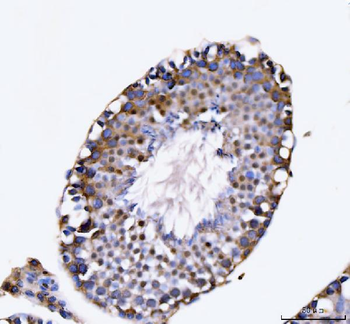

100 μl, 50 μl, 200 μl - ATF4 Recombinant Rabbit Monoclonal Antibody [orb704304]Featured

FC, ICC, IF, IHC-Fr, IHC-P, WB

Human

Mouse

Rabbit

Recombinant

Unconjugated

50 μl, 100 μl - MARK3 Recombinant Rabbit Monoclonal Antibody [orb704310]Featured